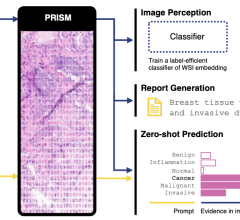

May 30, 2024 — Paige, a global leader in end-to-end digital pathology solutions and artificial intelligence (AI) ...

May 30, 2024 — Researchers from Penn Medicine’s Abramson Cancer Center (ACC) and the Perelman School of Medicine at the ...